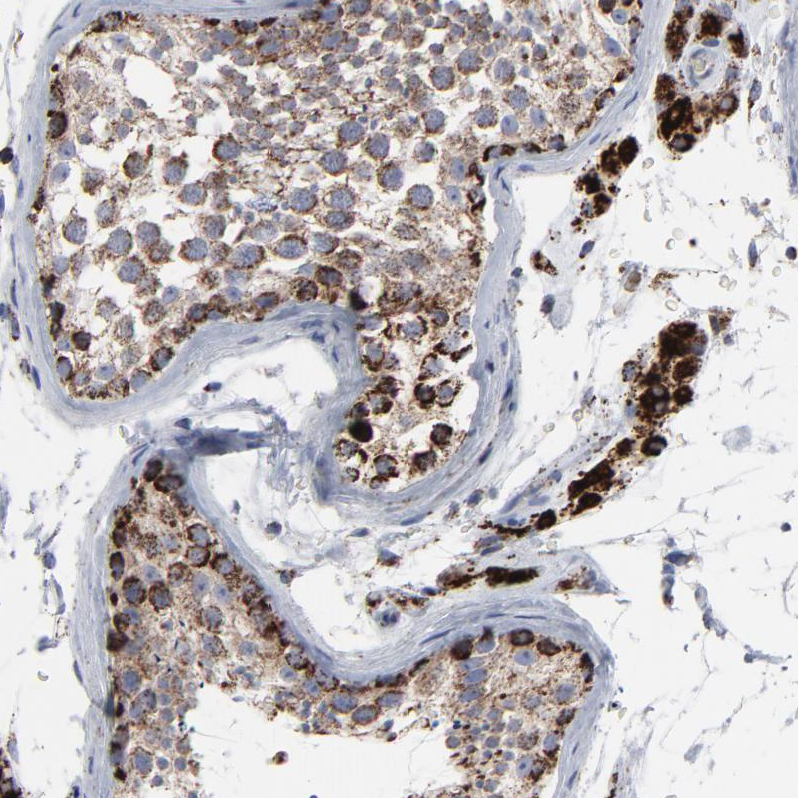

Immunohistochemical staining of human adrenal gland shows strong granular cytoplasmic positivity in glandular cells.